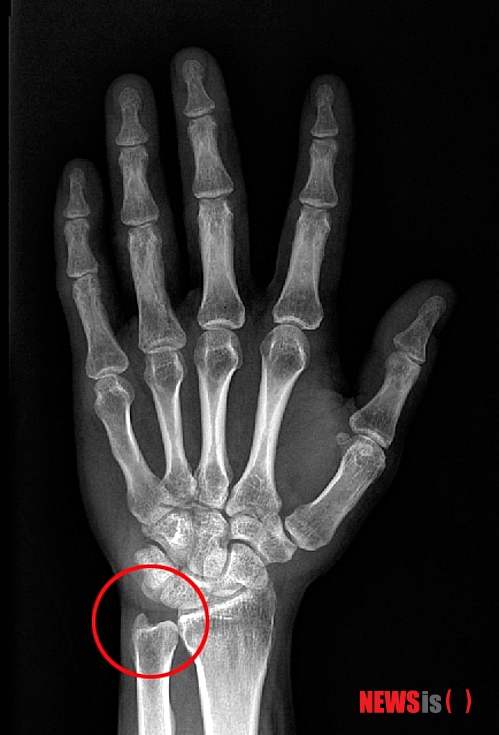

척골충돌증후군은 말 그대로 척골이 충돌한다 해서 붙여진 이름으로 팔꿈치부터 손목까지 이어진 척골이라는 뼈의 손목 쪽 끝부분이 자라나면서 손목뼈와 충돌하는 것을 말한다. 가장 큰 원인은 지속적이며 반복적인 손목의 무리한 사용으로, 이로 인해 척골의 끝부분이 자라나는 것이다. 그 길이는 5㎜ 이상으로 아주 작은 차이지만 손목의 일상적인 사용도 힘들게 할 정도로 통증을 줄 수 있다.

【서울=뉴시스】척골충돌증후군

혹시 그동안 손목통증으로 고생 중이었다면 손목 안쪽 아래의 뼈를 살펴볼 필요가 있다. 뼈가 살짝 나와 있고 그 부위에 통증이 심하다면 척골충돌증후군을 의심해 봐야 한다.